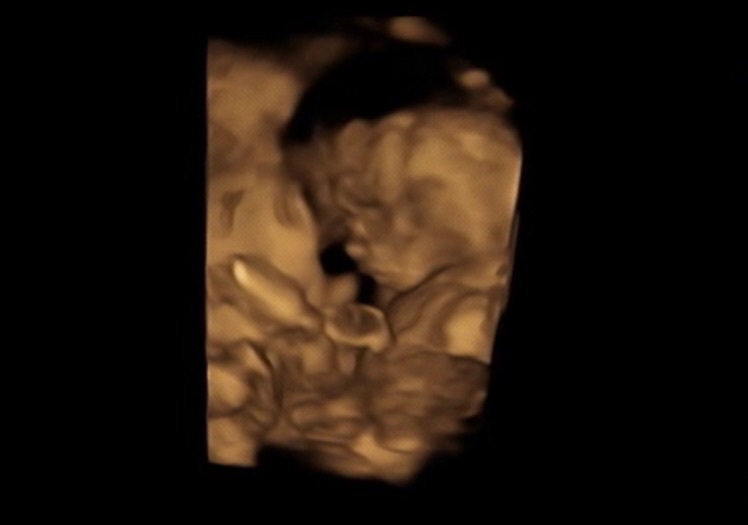

顔は かなり娘に似てそう 。

エコーを見ると

娘を 見ているみたいで

面白い ❤︎

これは まだまだ 体も写ってる小さい頃の 。

今は 顔だけ

どーん !

だから あんまり 体の動きとか

見れなくて さみしい 😌